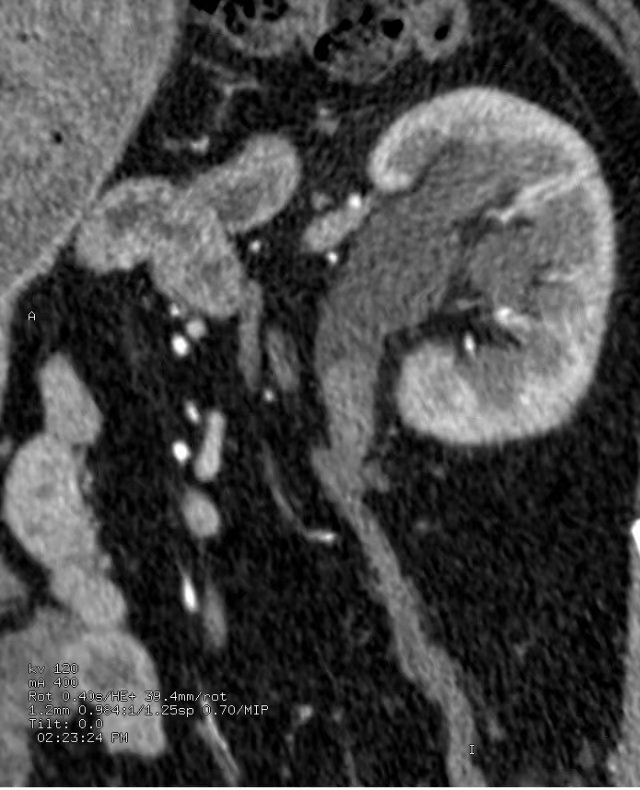

上图为泌尿系平扫后重建,可见左侧输尿管中段结石。

下图为静脉注射造影剂后,进行一定时间延迟后进行扫描、重建,见结石影与造影剂对比良好。